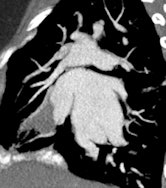

MDCT using a low radiation dose protocol is the best diagnostic tool for assessing the central airway, cardiovascular and mediastinal abnormalities, and the lung parenchyma in children, and the relevant information can be acquired with a single-volumetric data set acquisition, she stated. Using thin-slice collimation acquisition with inherent isotropic resolution, the image data can be manipulated and reformatted to display 2D and 3D images with the same spatial resolution as the axial images, thus enhancing diagnostic accuracy and providing data that can be used in presurgical planning and patient management.